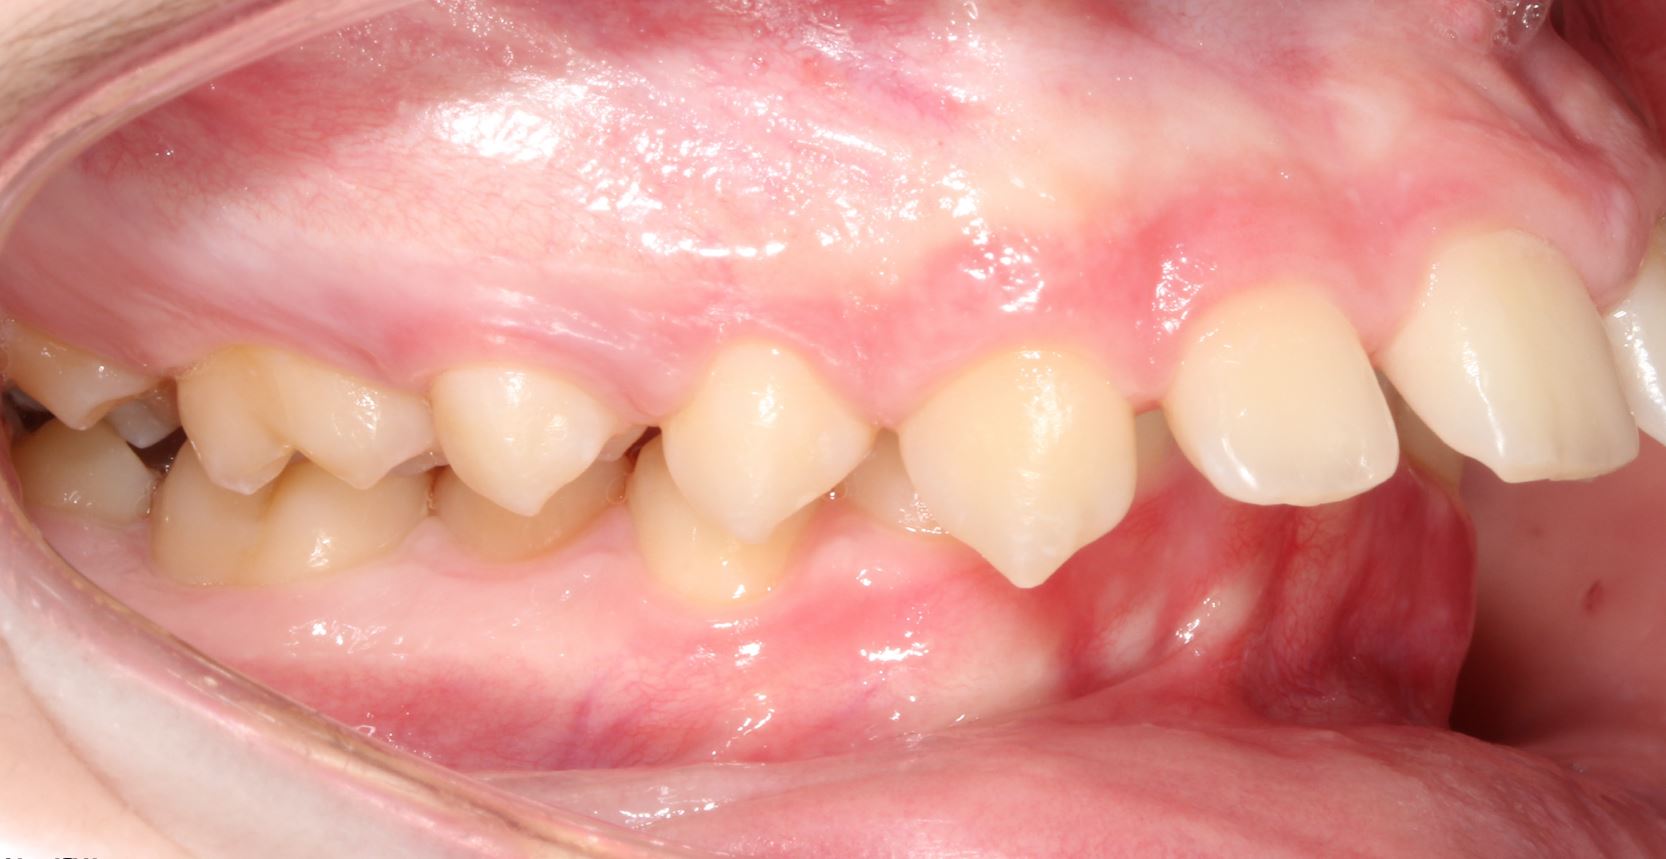

Deep Overbite and Crossbite